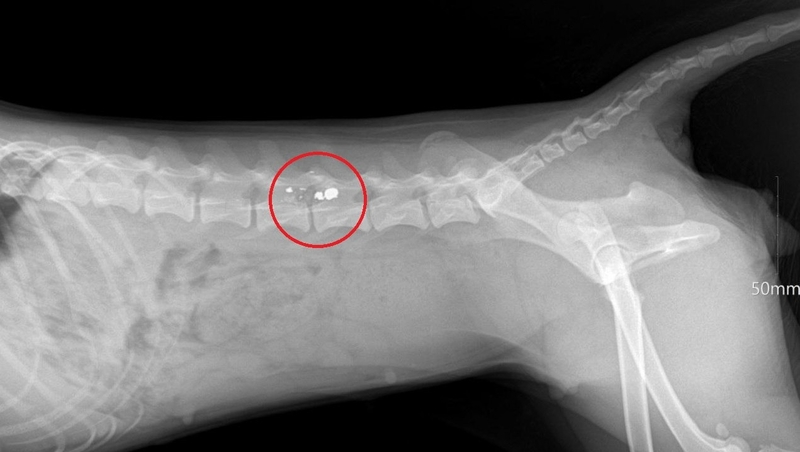

Женщина из села Горнозаводского в октябре пожаловалась в полицию, что сосед расстрелял её собаку. Раненый пёс истекал кровью и волочил ноги на глазах у детей. Полицейские задержали местного жителя, который объяснил свою жестокость местью. Собака ранее душила его кур, которые гуляли по улице. Он решил, что животное бездомное, и когда снова заметил пса недалеко от стайки кур, выстрелил из винтовки. Ветеринары, осмотревшие животное, диагностировали паралич тазовых конечностей.Дробь попала в позвоночникФото: Полиция СтавропольяРасследование дела завершено, документы передали в суд.